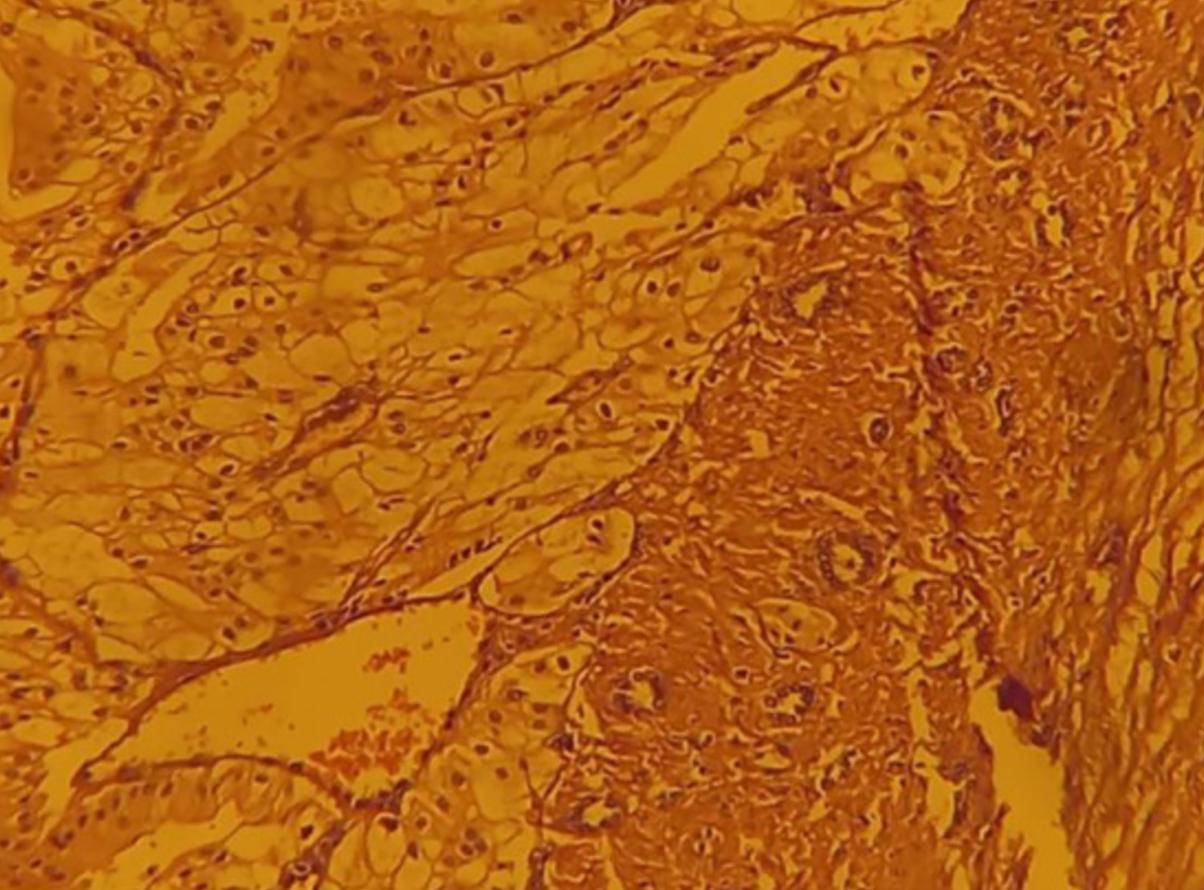

肿瘤的病理检查(图4)证实2级RCC,具有透明细胞亚型,直径6.0cm,并粘附0.5 cm周围组织。手术持续215 分钟,估计失血量为200 mL。患者7天后出院。在16个月的随访期间,患者报告没有泌尿系统症状。手术后的一系列影像学检查未见肿瘤的转移或生长。他的SCr水平稳定在2 mg/dL上下。

图4 显微镜检查,Van Gieson染色,显示具有透明细胞亚型的2级肾细胞癌